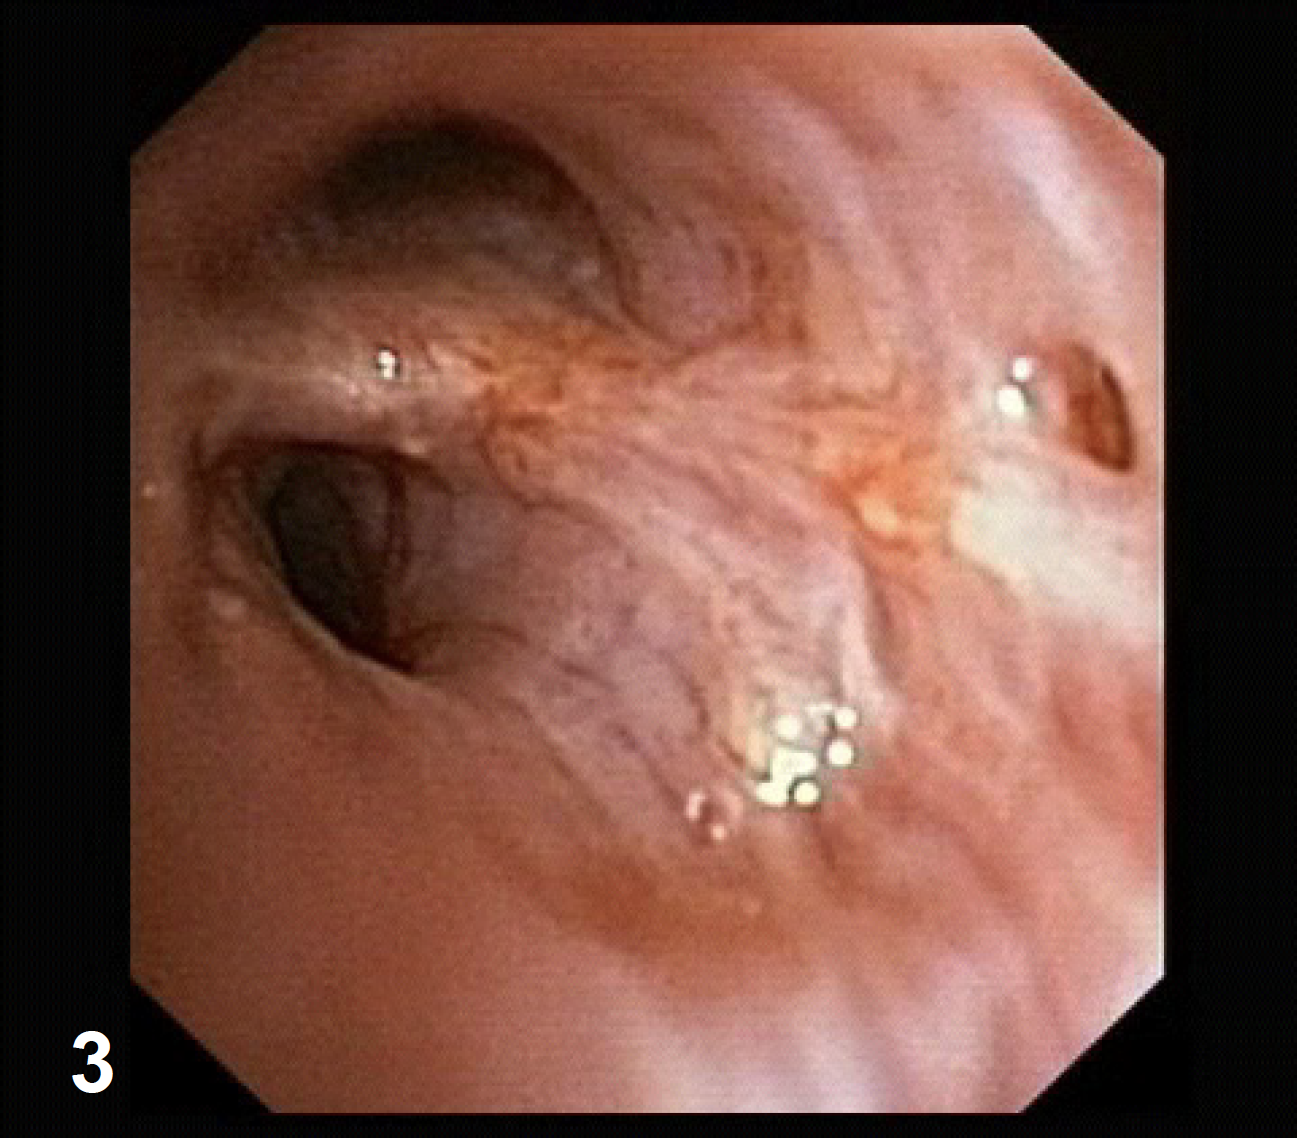

Videobroncoscopia

La videobroncoscopia consecutiva en el centro pulmonar mostró estructuras sospechosas de la mucosa.

EBUS descriptivo con sonda en miniatura de escaneo radial revela cáncer microinvasivo [fig 3,4].